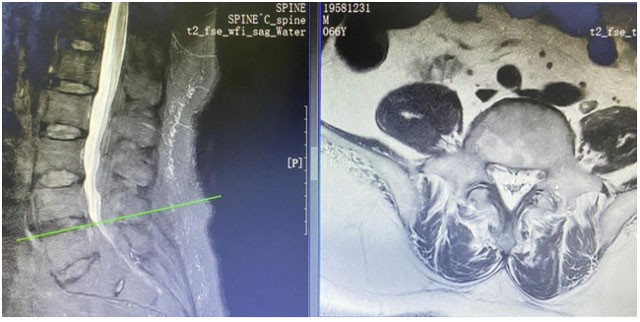

巨野县中医医院骨伤一科:攻克罕见病难题,成功救治椎管内脂肪增多症患者

近日,巨野县中医医院骨伤一科成功救治了一位罕见的椎管内硬膜外脂肪增多症患者,为患者带来了新生,也再次证明了医院在疑难病症诊治方面的卓越实力。患者是一位66岁的男性,多年来深受下肢瘫痪和大小便失禁的病痛折...